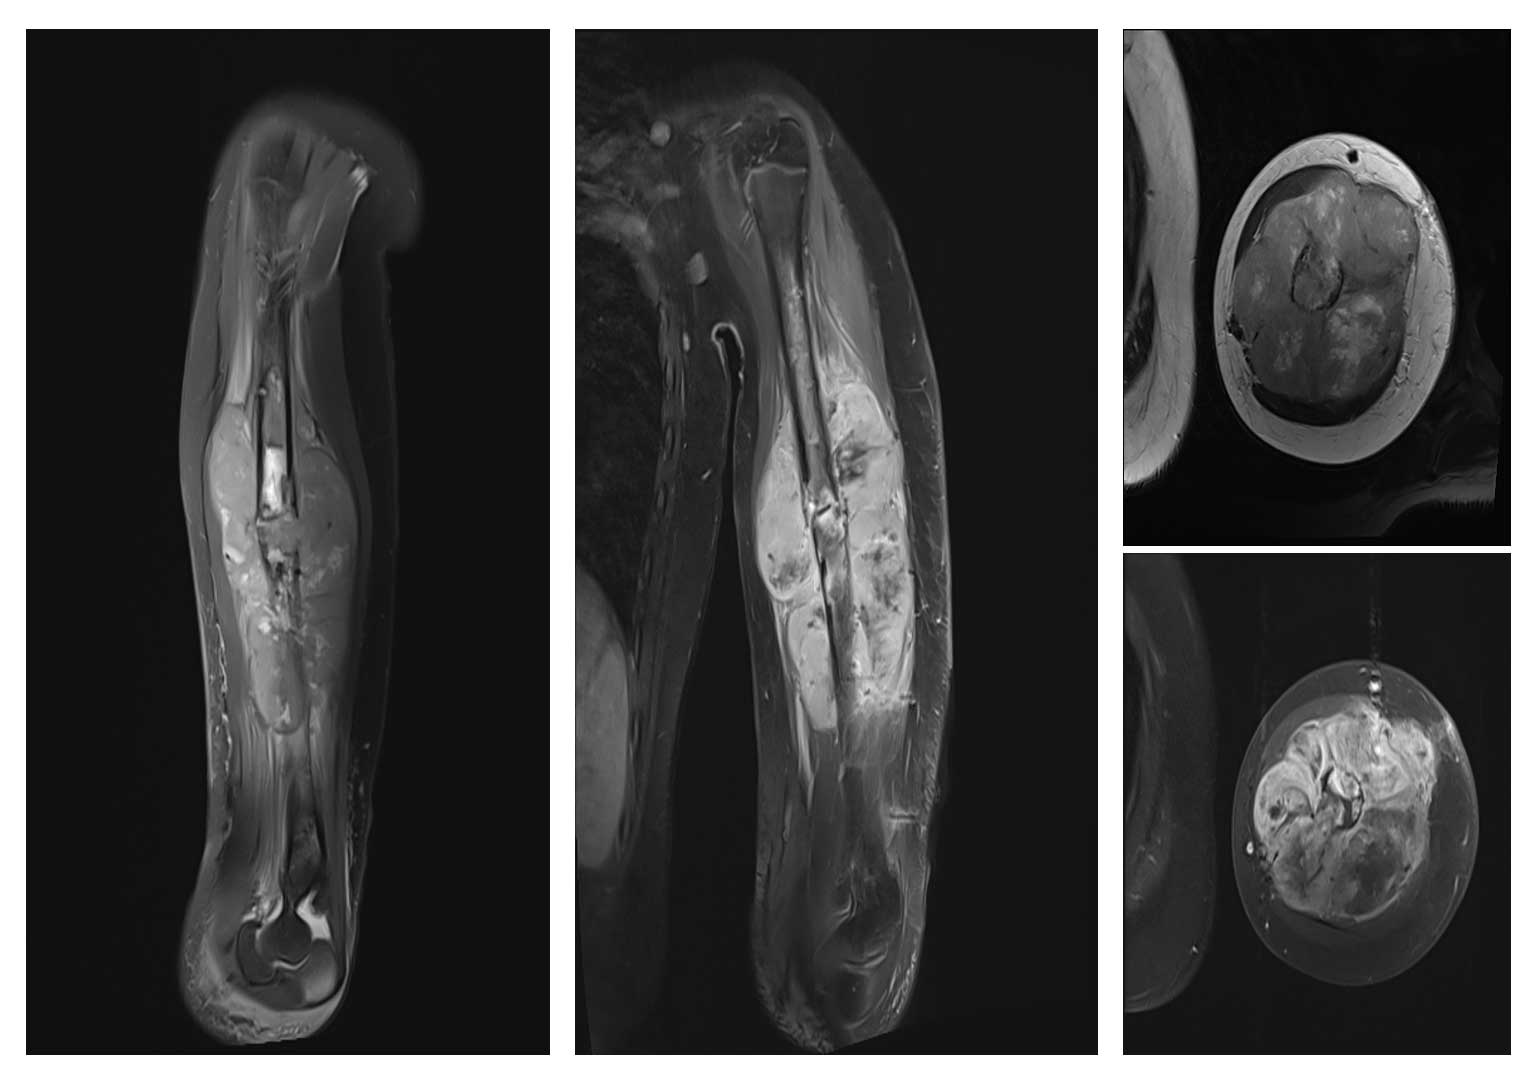

Ameliyat Öncesi: MR’da aynı lokalizasyonda kemikte patolojik kırığa neden olan heterojen, büyük boyutlu yumuşak doku komponentinin eşlik ettiği damar sinir paketini iten tümör dokusu görülmekte.